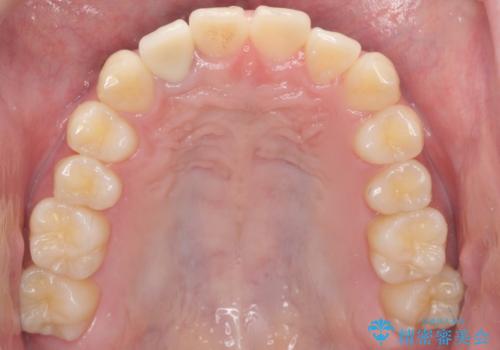

自然な仕上がりにご満足頂けました。

治療終了時には「修正や仮付けをしてもらえて納得のいく治療を受けられました。この病院にして良かったです!」とおっしゃって下さいました。

クラウンの種類:オールセラミッククラウン スペシャル